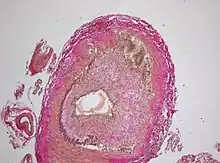

The gold standard for diagnosing temporal arteritis is biopsy, which involves removing a small part of the vessel under local anesthesia and examining it microscopically for giant cells infiltrating the tissue.[23] However, a negative result does not definitively rule out the diagnosis; since the blood vessels are involved in a patchy pattern, there may be unaffected areas on the vessel and the biopsy might have been taken from these parts. Unilateral biopsy of a 1.5–3 cm length is 85-90% sensitive (1 cm is the minimum).[24] Characterised as intimal hyperplasia and medial granulomatous inflammation with elastic lamina fragmentation with a CD 4+ predominant T cell infiltrate, currently biopsy is only considered confirmatory for the clinical diagnosis, or one of the diagnostic criteria.[11]